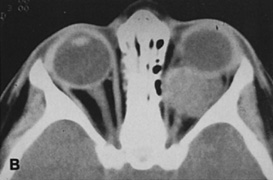

Fig. 16. A. Patient with right orbital cellulitis. B. Coronal CT scan demonstrating subperiosteal abscess formation from frontal and ethmoidal sinusitis. C. Frontoethmoidal orbitotomy incision marked for abscess drainage.

The periosteum is exposed and incised with a Freer elevator and then is reflected off the bone posteriorly. It is generally quite adherent to the curved contour of the medial canthal bones, especially at the medial canthal tendon. The anterior lacrimal crest is encountered inferiorly. Care should be taken not to damage the lacrimal sac with the elevator. The posterior lacrimal crest is visible behind the sac. Adequate mobilization of the periosteal connections to the anterior lacrimal crest gives a large area of exposure. The periosteal elevation is carried superiorly in the area of the trochlea. Elevation of the periosteum opens the subperiosteal space. Blood or pus caused by fracture or infection, if present in this space, is encountered at this point.

Elevation of the periorbita along the medial orbital wall posterior to the lacrimal sac progresses easily. Orbital fractures involving the thin ethmoid bone are seen at this point. The anterior ethmoidal artery is seen at the junction of the ethmoidal and frontal bones where the orbital roof meets the medial orbital wall (see Fig. 7). Usually it is found on a line extending posteriorly from the superior border of the medial canthal tendon. This artery either should be thoroughly cauterized with the bipolar cautery or clipped with a vascular clip before cutting. As the dissection in the subperiosteal space moves posteriorly, the orbit narrows. The posterior ethmoidal artery is identified. This is a reliable landmark for the optic foramen, which lies approximately 5 mm behind the ethmoidal artery.

Indications

The frontoethmoidal medial orbitotomy allows access for a variety of procedures in the subperiosteal and peripheral surgical spaces and sinuses (Fig. 17). Its main use is for processes involving both the frontal or ethmoid sinuses and the orbit. Entrance into the subperiosteal space is obtained easily. Drainage of subperiosteal blood or pus occurs as the space is entered.